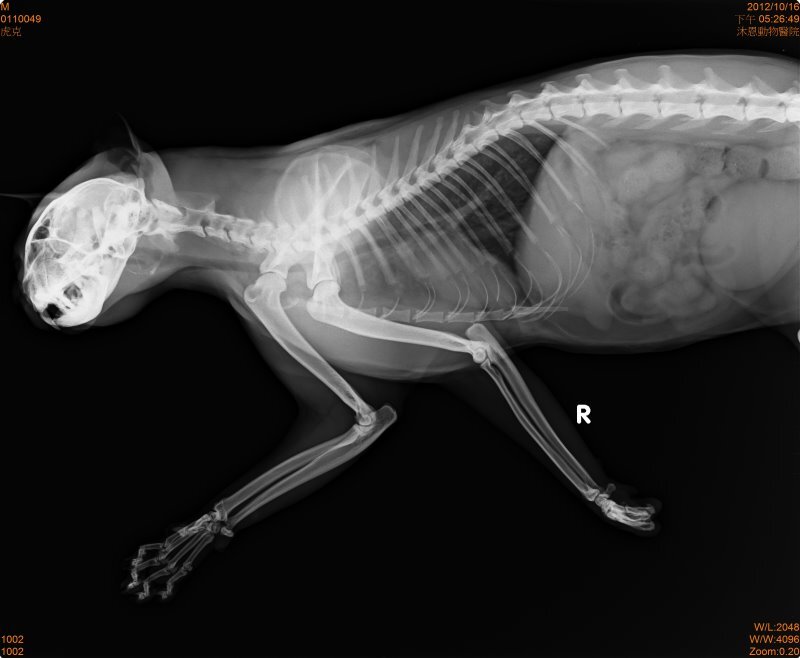

主題: 斷掌的虎斑公貓--虎克 申請者姓名: 蔡葦澄 花色: 申請日期: 2012-11-16 01:30:49 申請者部落格: 申請者臉書網址: 所在縣市/合作醫院: 台北市/其他院所醫助專案(醫院請先MAIL溝通) 治療費用: 12800元 需求人數: 28人 已結案 (2013-06-13 11:58:04) 報名人員: April Tsung(已付款)、Sean Chun-hsiang Yo(已付款)、阿蓋 (已付款)、chiawei(已付款)、柳佳豪(已付款)、Ting-Hsuan Tseng(已付款)、Yiling Tsai(已付款)、leehiromi(已付款)、謝沛豈(已付款)、黃小紅(已付款)、Joyce Chung(已付款)、Monica Hu(已付款)、clement(已付款)、shuwen(已付款)、Corrie Tan(已付款)、Carol Kuo(已付款)、Chiao-Hsin Yu(已付款)、斑斑姊(已付款)、柯元傑(已付款)、春卷(已付款)、Patrick Liu(已付款)、Ching Yi Hsieh(已付款)、Sean Chun-hsiang Yo(已付款)、Angel Li(已付款)、喵媽(已付款)、喵媽(已付款)、Summer(已付款)、chapi(已付款)、 候補人員: 動物病情說明: 網友求援在大安區SOGO附近的安東街,有美短紋路的貓咪左眼受傷需要醫療。前去該地區騎車繞了好幾圈並沒有看到眼睛受傷的貓,從超商旁騎過看到一個影子閃進防火巷(有鐵門)放了點罐頭,貓有跑出來吃,設了誘捕籠躲在旁邊,看見貓一拐一拐地走進去,門關起來後也沒有很激動,稍微看一下發現貓貓沒有手掌,X光檢查後將傷口做縫合,因為斷處還保有肉墊,可供行走用,不需截肢,等傷口復原進行結紮,目前恢復狀況良好以R回原處,醫療費用還請各位幫忙。